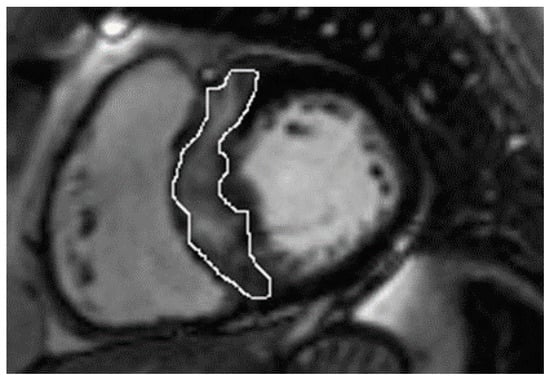

In the whole group, LGE was present in 37 (74%) patients. Patients with nsVT had a larger extent with respect to LGE (Table 2). However, the patients did not differ in native and post-contrast T1 times and ECV values, and the mere presence of LGE only showed a trend towards significance. Figure 1 and Figure 2 present examples of images obtained in the CMR studies.

Figure 2.

Native and post-contrast contours in the mid-myocardial area. The left ventricular cavity is shown (orange in native T1 mapping and dark blue in post-contrast T1 mapping) to enable the derivation of blood and myocardial T1 values. Standardized ROIs are placed in the septum to measure native (A) and post-contrast T1 times (B).